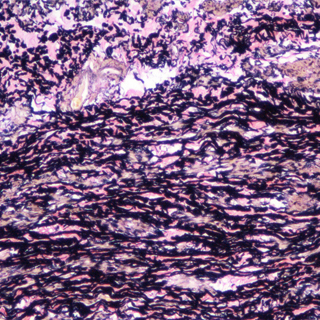

EVG染色样片参考:

EVG-丽春红复染

EVG染色实验结果:

弹性纤维呈蓝黑色;胶原纤维呈红色;背景呈淡黄色。